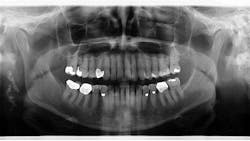

Assessment of the panoramic radiograph revealed two corrugated, irregularly shaped radiopaque masses on the right posterior angle of the mandible, each measuring approximately one inch in length. The area was not tender to palpation, and the patient had no knowledge that the lesions were there.

**See image below**1